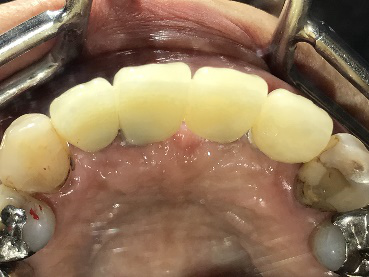

男性Kさん 50代(インプラント)

歯がグラグラするところ、むし歯のところ、しみるところ、被せ物がとれたところ、歯茎が腫れて血が出るところ、歯が抜けているところがある。すべて治したい。

治療内容

残っている歯を抜歯し、上下インプラント治療をしました。

所感

歯周病が進行している歯、むし歯が進行している歯がほとんどで、レントゲンを撮り、詳しく診てみると、ほとんどの歯を保存することができないことがわかりました。抜歯後は、入れ歯かインプラントの方法があります。治療開始前に患者さんに詳しく現状を説明し、治療法についてじっくり相談しました。自分の歯と同じような感覚で食事できるインプラント治療を選択されました。治療後、表情がとても明るくなり、口元がとても自然で10歳以上若返ったように感じました。「時間はかかりましたが、インプラントにして本当に良かったです!」と素晴らしい笑顔でお話ししてくださいました。

上顎:¥3,280,000(税込)

下顎:¥3,280,000(税込)